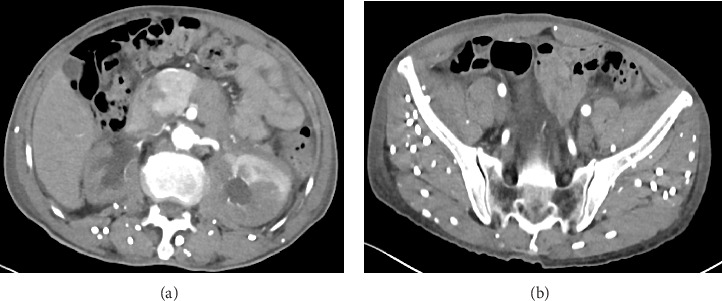

Cysticercosis refers to a disease caused by the larvae of Taenia solium parasitizing various tissues and organs of the human body. It is reported that cysticercosis is most commonly caused by the central nervous system, and retroperitoneal fibrosis is rare. We report a case of retroperitoneal fibrosis caused by cysticercosis and a urinary tract obstruction caused by retroperitoneal fibrosis, which was successfully relieved by transurethral stenting. The complex pathophysiological mechanism of cysticercosis-induced retroperitoneal fibrosis requires further study. In the diagnosis and treatment of the disease, it is very important to consider the patient's epidemiological history and the presence of parasite infection.